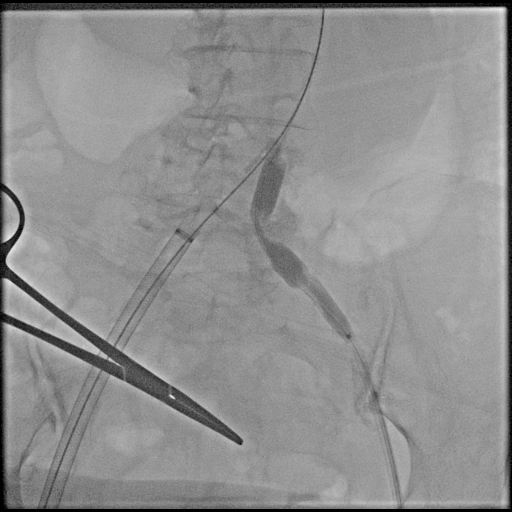

Under general anesthesia, bilateral common femoral arteries were accessed percutaneously under ultrasound guidance, and the pre-close technique with Perclose ProGlide (Abbott Vascular, USA) was applied. Angiography confirmed a large infrarenal AAA and left common iliac artery with severe stenosis (>70%) and marked tortuosity, while the right iliac was relatively straight. Guidewire advancement through the left side was difficult due to narrowing and vessel curvature.

Percutaneous transluminal angioplasty (POBA) was performed on the proximal left common iliac artery using a 10 ¡¿ 80 mm Mustang balloon (Boston Scientific, USA) inflated and showing a balloon-waist formation consistent with a tight, fibrotic lesion. After gradual dilation up to 6 atm, the waist resolved and the lumen expanded, allowing smooth wire and sheath passage. The SEAL NOVUS stent-graft system (S&G Biotech, Korea) was used, with the main body (24 ¡¿ 50 mm) introduced via the right common femoral artery. Two flared iliac limbs, 12(18) ¡¿ 100 mm on the left and 12(16) ¡¿ 80 mm on the right, were deployed in a ballerina (crossed-limb) configuration to accommodate left-sided tortuosity and prevent kinking. During contralateral limb cannulation, angiography was performed within the main body to confirm the wire course inside the graft before advancing the sheath. Completion angiography demonstrated a Type Ia endoleak, treated with proximal neck flaring using a Coda LP balloon (Cook Medical, USA) under a rapid inflation–deflation technique to optimize sealing and prevent graft migration. Final angiography showed excellent proximal seal and bilateral flow, and follow-up CTA confirmed durable aneurysm exclusion without endoleak.